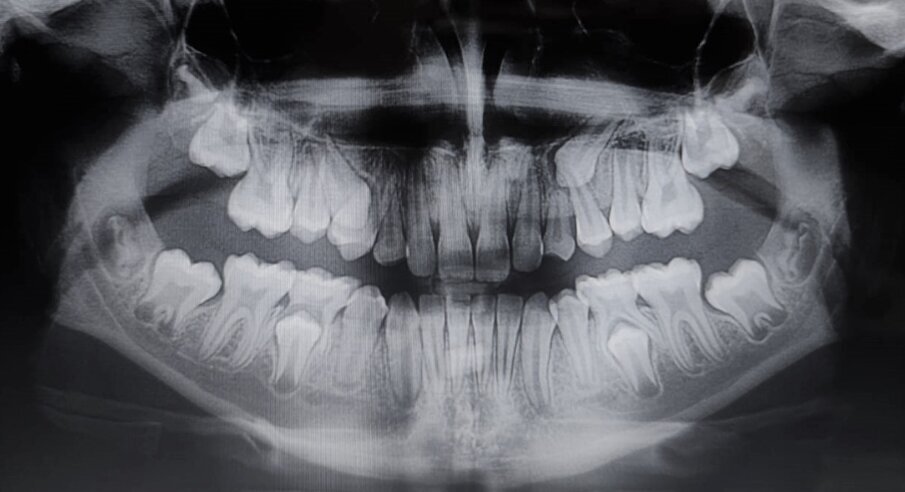

Eziologia La trasposizione dentale sembra avere una eziologia multifattoriale dove un ruolo importante è ricoperto dalle cause genetiche e dalle cause ambientali9. Alcuni Autori avvalorano maggiormente la teoria genetica10, sostenendo che un’alterazione nello sviluppo dentale produca, contestualmente alla trasposizione, varie anomalie dentali, quali ad esempio: agenesie dentali, incisivi laterali conoidi, etc. 2,7,11. Inoltre, l’interessamento bilaterale dello stesso dente, la presenza di trasposizione dentale in pazienti sindromici, come nella sindrome di Down12 o nella displasia cleidocranica13, il riscontro dell’anomalia in gemelli monozigoti14, sono altre evidenze che possono confermare l’eziologia genetica. In Figg. 1a, 1b è riportato un interessante caso di due gemelle eterozigoti che mostrano entrambe trasposizione canino-premolare mascellare e ritenzione canina.

Figg. 1a, 1b - Rx-OPT della paziente 1 (A) e della paziente 2 (B) gemelle di anni nove e mezzo entrambe in trattamento ortodontico intercettivo. Si nota la particolare e contemporanea presenza sia della trasposizione canina-premolare sia della ritenzione canina superiore.